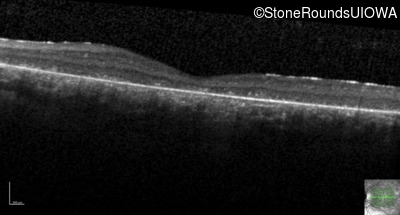

Age at visit: 8 years

This 8 year old girl had normal vision until age 6 when she failed a school vision screening. That year, she was able to play softball well, but this year she often loses sight of the ball and is often hit by it.